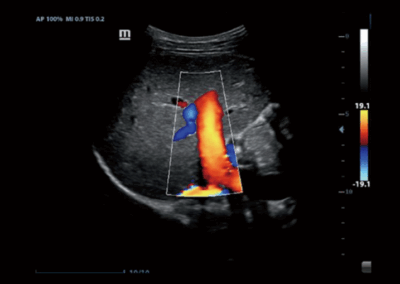

Z60

Sistema de diagnóstico ecográfico.

El sistema Z60 es una buena opción para aquellos que requieren un rendimiento de imagen de alta calidad, una movilidad simple y asequibilidad cuando se trata de imágenes ecográficas avanzadas. Con configuraciones completas y un diseño integrado, el Z60 es el resultado de los esfuerzos continuos y decididos de Mindray para hacer que la atención médica primaria sea más eficiente, eficaz y accesible para todos.